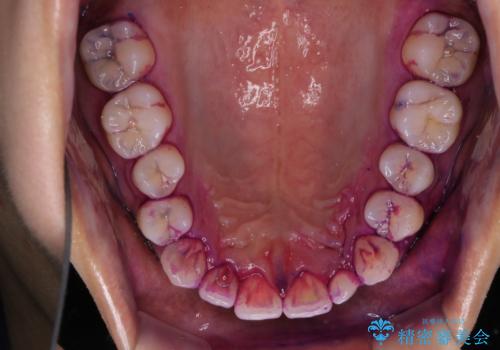

今後、ホームホワイトニング予定との事で、クリーニングPMTC(保険適応外)60分コースを行いました。汚れを取り除き、ご自身の本来の歯の表面になることでツヤがでます。

歯の表面に汚れがついたままホワイトニングを行うと、ホワイトニングの効果が出づらいことがあります。

汚れがついたままだと、虫歯・歯周病・口臭などの原因にもなります。歯科医院での、定期的なクリーニングを行うことが大切です。